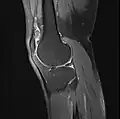

Imaging

MRI

Both anterior cruciate ligament (ACL) and posterior cruciate ligaments (PCL) are hypointense on both T1 and T2 weighted images of MRI. However, some high signal striations are often seen at the distal part of the ACL, making ACL higher intensity than PCL on MRI scans.[20]